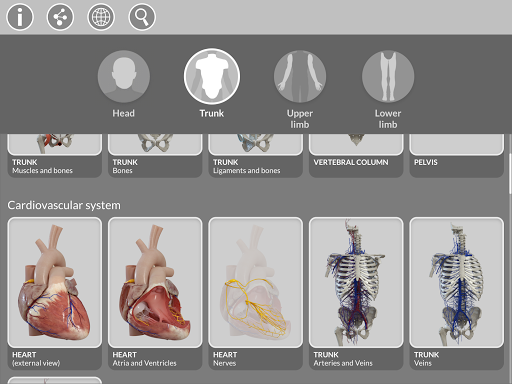

La subdivision par régions et les vues prédéfinies facilitent l'observation et l'étude de parties individuelles ou de groupes de systèmes et les relations entre différents organes.

MODÈLES ANATOMIQUES 3D

• Système musculo-squelettique

• Système cardiovasculaire

• Système nerveux